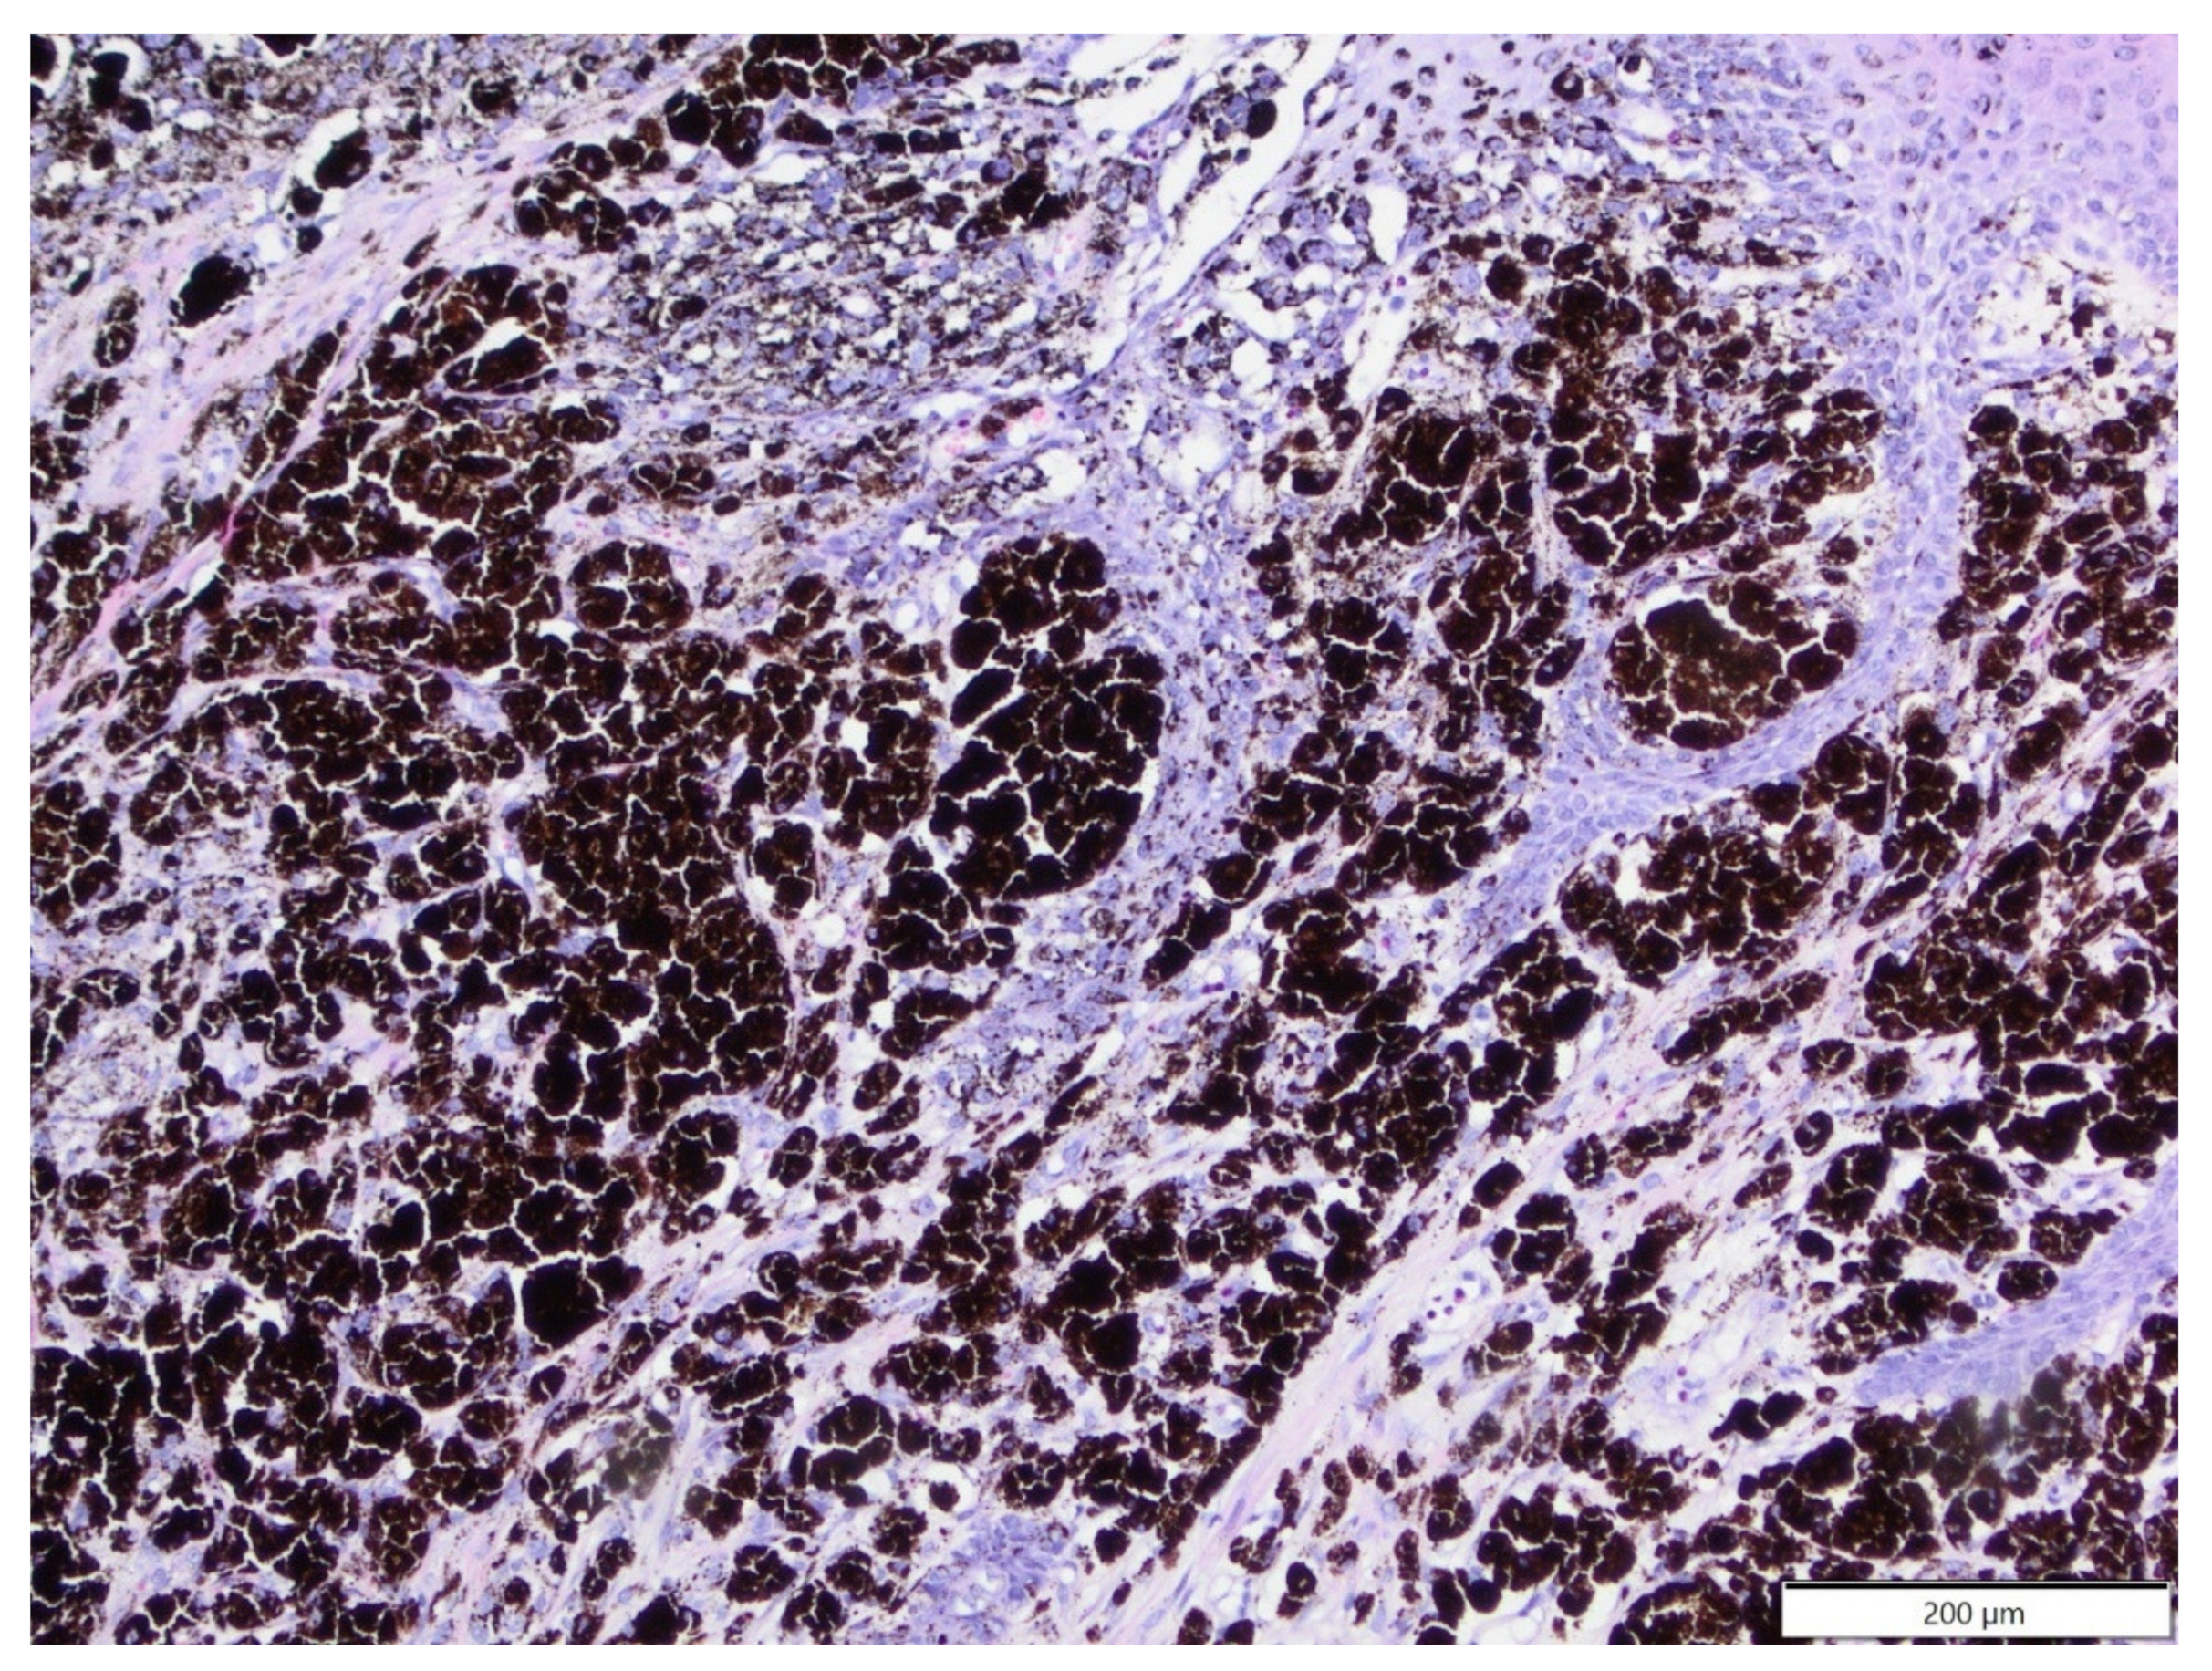

3.2. Rats

| 2 | Histiocytic sarcoma | 3.8% | 1 | 1 | 20 months |